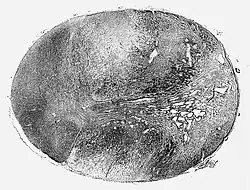

![]() Glioblastoma arising in an astrocytoma. This spinal cord exhibits both a lightly staining microcystic astrocytoma as well as a darkly staining glioblastoma. | |